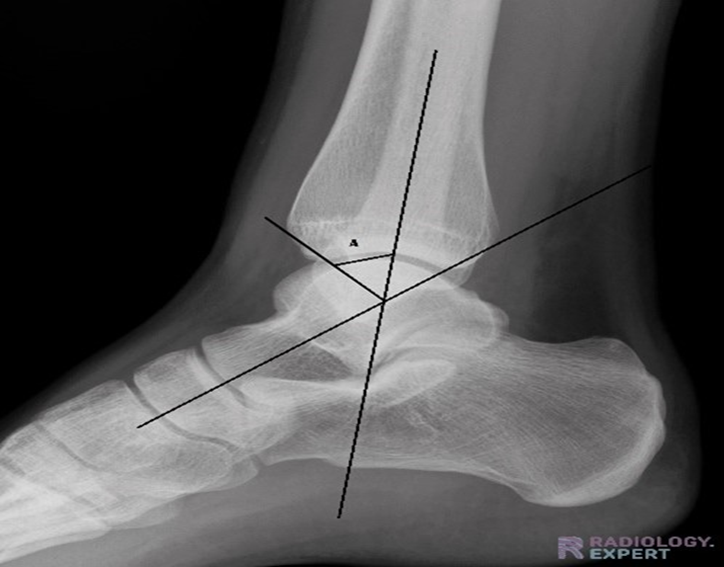

A complete clinical and neurological examination was done for all the patients. The signs and symptoms of local manifestation, such as pain, swelling, and restriction of motion were recorded. For all patients radiographs of Ankle Antero-posterior and lateral views were taken. X-ray Foot Antero-Posterior and lateral views were also taken for all patients to rule out associated Subtalar arthritis. The allocation of the type of fixation for the subject was done with double blinding. Radiologic outcomes were measured by: (1) Rate of union, (2) Rate of adjacent joint arthritis, (3) Alignment of the ankle joint. Functional outcomes were measured by using the AOFAS score (American Orthopedic Foot and Ankle Society score). Subjective assessments of the patients were done utilizing the Cumberland Ankle Instability Tool (CAIT). This evaluation was performed based on preoperative radiologic data and at postoperative clinical visits at 2 mo, 6 mo, and 12 mo required postoperatively. Ankle joint AP and lateral view X-rays taken while the patient was bearing weight were used to determine the ankle joint's alignment after surgery. In the AP projection, the angle between the tibia's long axis and a line parallel to the talus's long axis is found. In the lateral projection, the angle between the tibia's long axis and a line that is perpendicular to the talus’s long axis is measured. Digitalized X-rays and measurement instruments are used to identify the ankle joint's axis in the AP and lateral views. When more than five degrees of valgus or any amount of varus malalignment is observed at the ankle joint in the AP view, it is considered malalignment. The angles were measured using a protractor application.

In this study, the angle between the tibia's long axis and a line parallel to the talus's long axis is determined in AP projection. The mean angle was 89.6 degrees (85-100 degrees) in the intramedullary nailing group and 91.4 degrees in the corticocancellous screw group. The angle between the tibia's long axis and a line that is perpendicular to the talus's long axis is measured in lateral projection. The mean angle was 40.5 degrees (30-45 degrees) in the intramedullary nailing group and 41.6 degrees in the corticocancellous screw fixation group.

Picture 2: Shows the angle between the tibia's long axis and a line that is perpendicular to the talus’s long axis